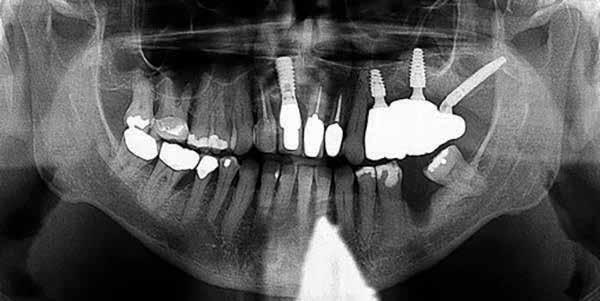

#13, #14 for ridge preservation. At a later date, three implant-supported crowns in close proximity were placed in these sites. Notably, the crowns were non-splinted. (Fig. 1).

In July 2021, the patient presented with mobile implants #12, #13 and #14 to his dental practitioner (Fig. 2). The implants were removed without bone grafting.

Fig. 1: May 2021. Panoramic radiograph shortly after placement of upper left #12, #13, #14.